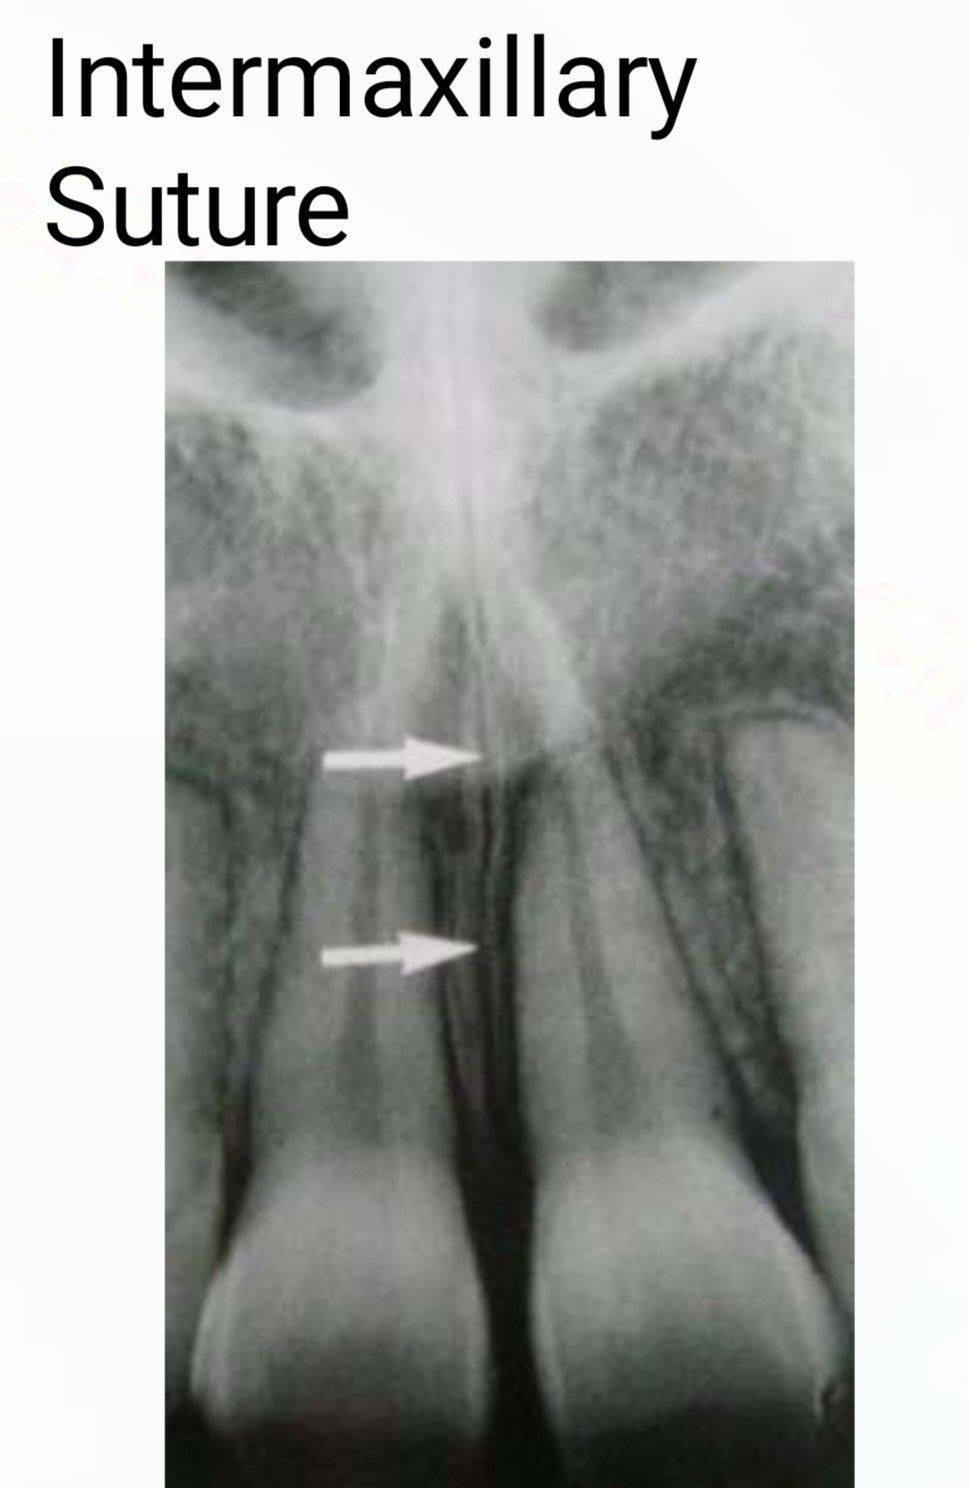

Intermaxillary Suture

The intermaxillary suture is a cranial suture, just below the anterior nasal spine, between the right and left maxillary bones clearly visible in this radiograph.